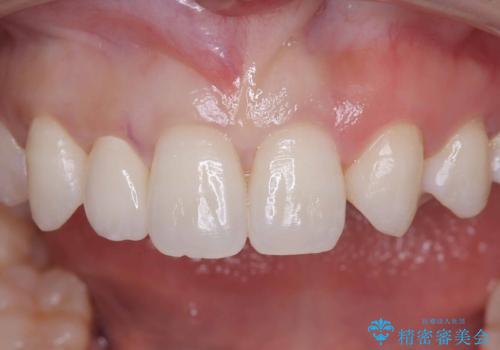

右上2が矮小歯だったので、オールセラミッククラウンで審美修復しました。

見た目が改善され、大変ご満足いただけました。